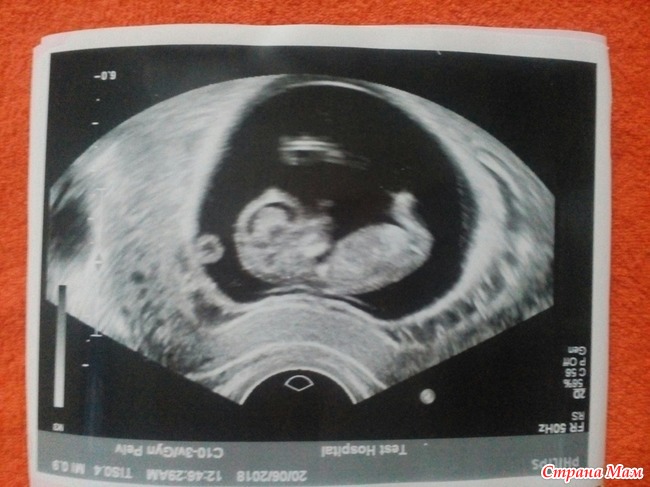

Итак, наш сегодняшний скрининг

Делала скрининг в соседнем городе, у нас не делают, отправляют в Салават. Там, к сожалению, фотографии не делают. Но я как знала!

Две недели назад сделала УЗИ (чисто для себя и собственного спокойствия) платно, там конечно и фото дали.